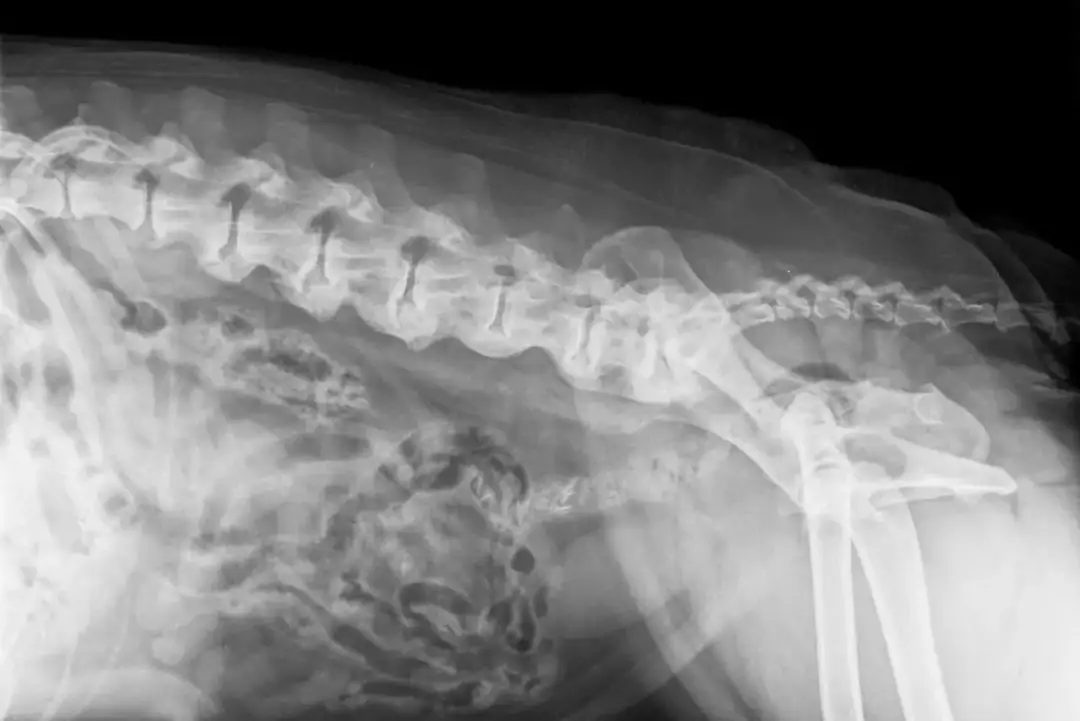

Spondyloza to, mówiąc najprościej, choroba zwyrodnieniowa kręgosłupa, która niestety bardzo często dotyka naszych starszych czworonożnych przyjaciół. Szczególnie predysponowane są do niej psy dużych ras, takie jak owczarki niemieckie czy boksery, ale może pojawić się u każdego psa w podeszłym wieku. Mechanizm choroby polega na tworzeniu się kostnych wyrośli, zwanych osteofitami, na krawędziach trzonów kręgów. Wyobraź sobie, że kręgosłup, który powinien być elastyczny, zaczyna się usztywniać i "zrastać" w mniej lub bardziej bolesny sposób. To właśnie te zmiany prowadzą do usztywnienia kręgosłupa i ograniczenia jego ruchomości.

W zaawansowanych przypadkach, niestety, osteofity mogą urosnąć na tyle, że zaczną uciskać na nerwy lub nawet rdzeń kręgowy. To z kolei prowadzi do silnego bólu, a w konsekwencji do problemów neurologicznych, takich jak niedowłady czy zaburzenia koordynacji. Musimy pamiętać, że spondyloza jest chorobą postępującą i niestety nieuleczalną. Dlatego też, jako właściciele, musimy skupić się na łagodzeniu objawów, spowalnianiu postępu zmian i przede wszystkim na poprawie komfortu życia naszego psa. To jest nasz główny cel w walce z tą dolegliwością.